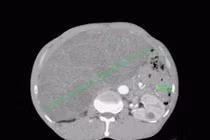

Khối u kích thước khổng lồ xâm lấn đại tràng phải, đè đẩy các tạng khác trong ổ bụng, chưa xâm lấn mạch máu lớn nên có thể cắt bỏ được.